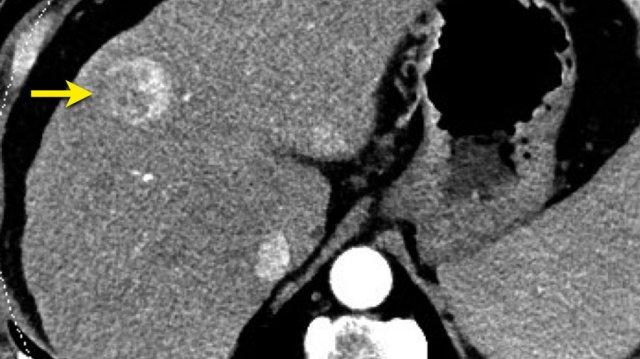

LI-RADS 3

Đây là một tổn thương tăng ngấm thuốc nhỏ khác không có bất kỳ đặc điểm bổ sung nào như thải thuốc (washout), vỏ bao (capsule) hoặc tăng trưởng vượt ngưỡng (threshold growth).

Tổn thương này cũng được phân loại là LI-RADS 3.

Hình ảnh thì động mạch, thì tĩnh mạch cửa và thì muộn của một tổn thương LIRADS 3.

Tại phân thùy 5 có một tổn thương dưới bao gan với ngấm thuốc động mạch mạnh mà không có thải thuốc ở thì tĩnh mạch cửa hoặc thì muộn.